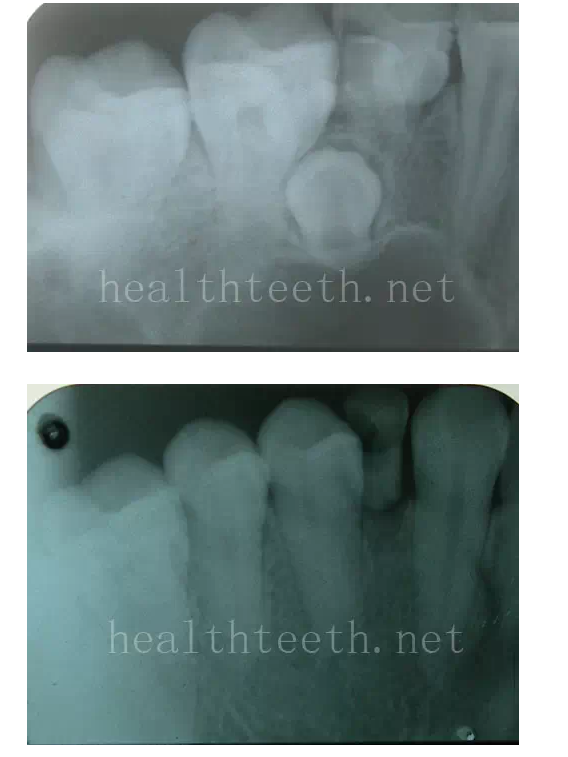

牙根折斷

烤瓷牙打樁修復(fù)后牙根折斷